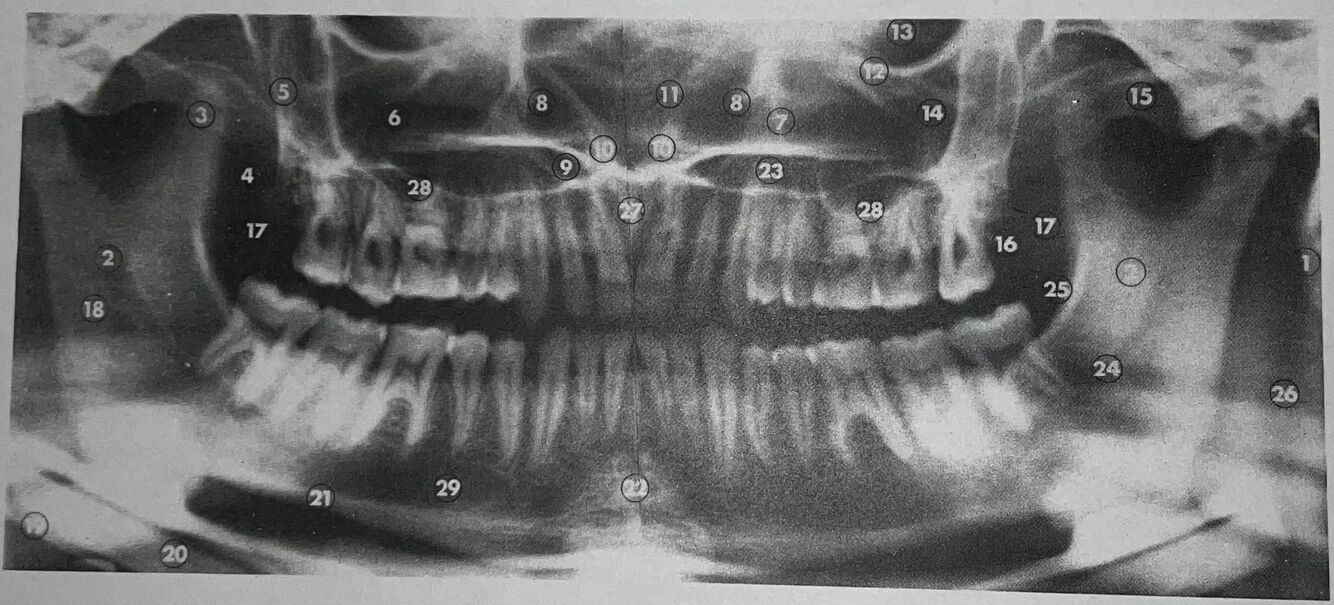

1

what is 1

mastoid process

2

what is 2

lingula

3

what is 3

coronoid process

4

what is 4

lateral pterygoid plate

5

what is 5

posterior wall of antrum

6

what is 6

antrum (maxillary sinus)

7

what is 7

anteromedial wall of antrum

8

what is 8

inferior concha

9

what is 9

floor of nasal fossa

10

what is 10

anterior nasal spine

11

what is 11

nasal septum

12

what is 12

infraorbital ridge

13

what is 13

orbital cavity

14

what is 14

malar process

15

what is 15

zygomatic arch

16

what is 16

maxillary tuberosity

17

what is 17

20

what is 20

21

what is 21

inferior border of mandible

22

what is 22

mental protuberance

what is 23

23

what is 24

mandibular canal

24

what is 25

internal oblique line

25

what is 26

superimposition of right jaw

26

what is 27

incisive canals

27

what is 28

floor of antrum

28

what is 29

mental foramen